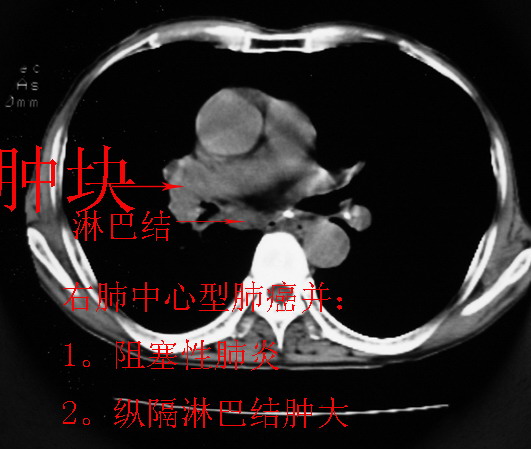

以下是引用同在2007-1-27 14:13:00的发言:[br]支持右侧中央型肺癌伴阻塞性病变.

以下是引用zjzjr在2007-1-27 16:56:00的发言:[br]支持右肺中心型肺癌伴阻塞性肺炎.